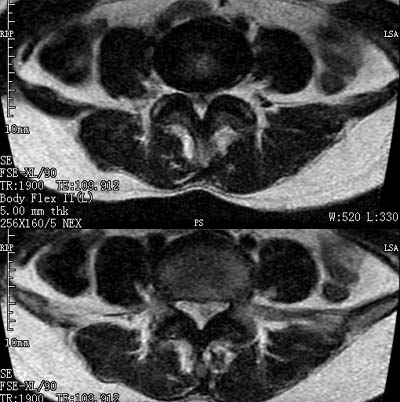

患者,女,50岁,左侧腹股沟及其下方疼痛、酸沉2年。

请各位战友看一下l4-5椎间盘后方椎管内是病灶吗?马尾神经到此处是不是终止了?

腰45椎间盘突出,后部影像可能是硬膜囊粘连引起的

l4/5椎间盘突出。后方硬膜囊受压改变。另外,该病人是否并发子宫肌瘤啊

腰45椎间盘突出,马尾终丝聚集:考虑蛛网膜炎症粘连

l4-5轻突,黄韧带增厚,蛛网膜炎症粘连可能

l4/5椎间盘突出;马尾终丝聚集,考虑蛛网膜炎所致。